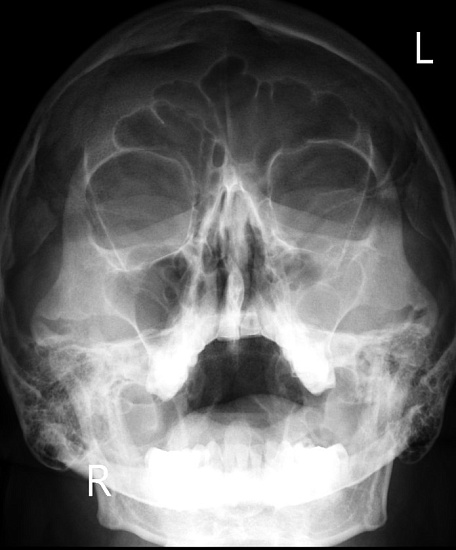

Рентгенография придаточных пазух носа

Рентгенография придаточных пазух носа – важный метод обзорного исследования состояния придаточных пазух носа.

Диагностическая услуга выполняется в одной проекции.

• подозрение на наличие патологии придаточных пазух носа: заложенность носа, головные боли, зеленое отделяемое, частые рецидивирующие воспалительные заболевания пазух;

• для исключения в пазухах острого или хронического воспалительного процесса, наличия кист, полипов, оценки развития системы придаточных синусов носа;

• рентгенография также позволяет оценить положение носовой перегородки.